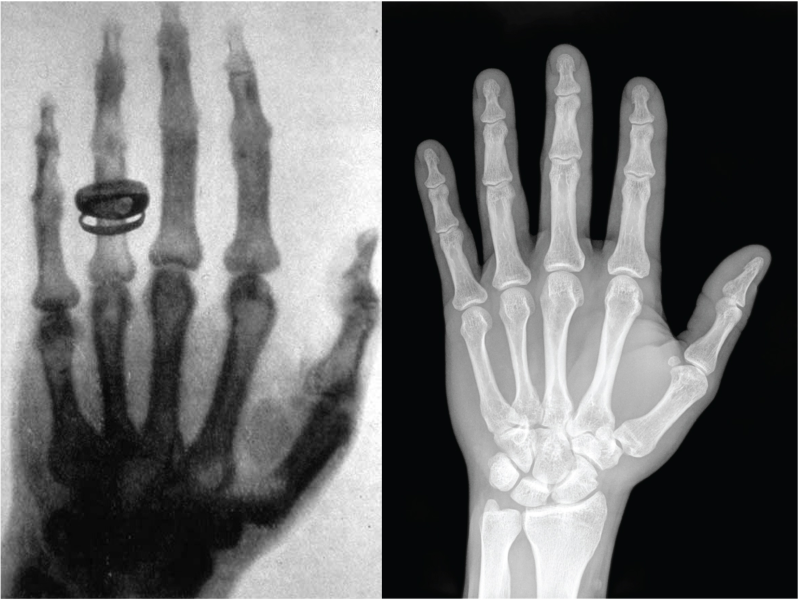

In 1895, the physicist Wilhelm Conrad Röntgen noticed a strange kind of radiation that could pass through paper and flesh, but not through bone. He called it X-radiation, because he didn’t know what it was.[1,2] Today, we still call it X-ray, although in some languages they are known as Röntgen light or Röntgen rays, and they are used every day in hospitals to make the inside of the body visible.

In a hospital, X‑ray imaging works a bit like shadow theatre. An X‑ray beam is sent through the body onto a detector. Soft tissue lets more X‑rays through, while bones absorb more. The detector records these differences, and the result is an image where bones appear bright and soft tissue appears darker.[6] The picture is created mainly by absorption, i.e. how much X‑ray intensity is lost on the way through.